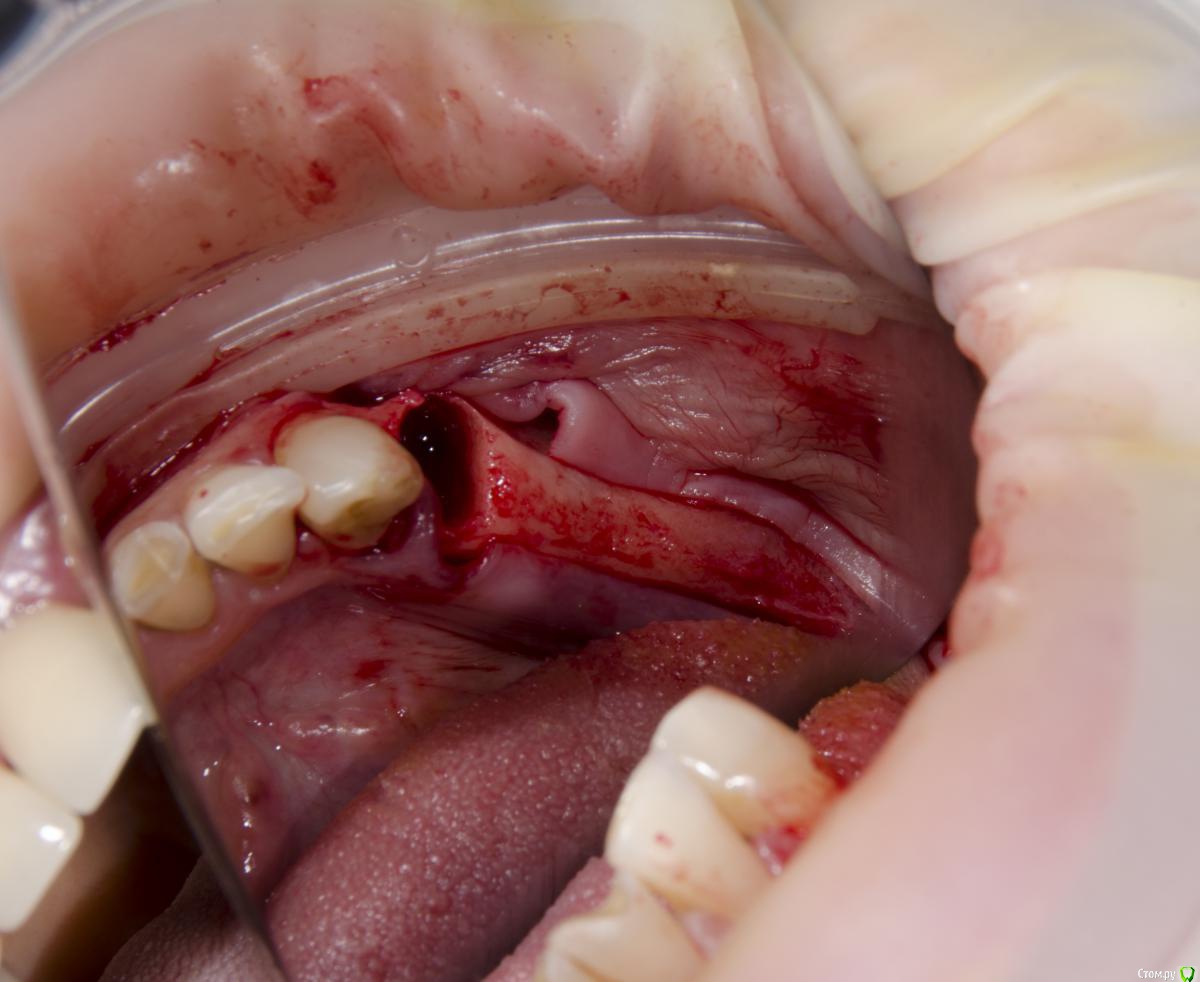

Доктор Добрых Дел Опубликовано 31 января, 2017 Поделиться Опубликовано 31 января, 2017 Аугментата пожалели мне кажется, объёма не особо добавится. Почему винты сразу не захотели? Вроде кости много. Ссылка на комментарий

Тимур86 Опубликовано 31 января, 2017 Поделиться Опубликовано 31 января, 2017 Это,как я понял,конечный результат Ссылка на комментарий

kamranchick Опубликовано 1 февраля, 2017 Автор Поделиться Опубликовано 1 февраля, 2017 Это,как я понял,конечный результатДа тим. Ссылка на комментарий

kamranchick Опубликовано 1 февраля, 2017 Автор Поделиться Опубликовано 1 февраля, 2017 Аугментата пожалели мне кажется, объёма не особо добавится. Почему винты сразу не захотели? Вроде кости много.Побоялся что если что то пойдет не так то придется все выгребать))Кости если честно не пожалел, не знаю куда он ушел, была ауто кость 2 грамма gen os и 0 5 альфа био графта Ссылка на комментарий